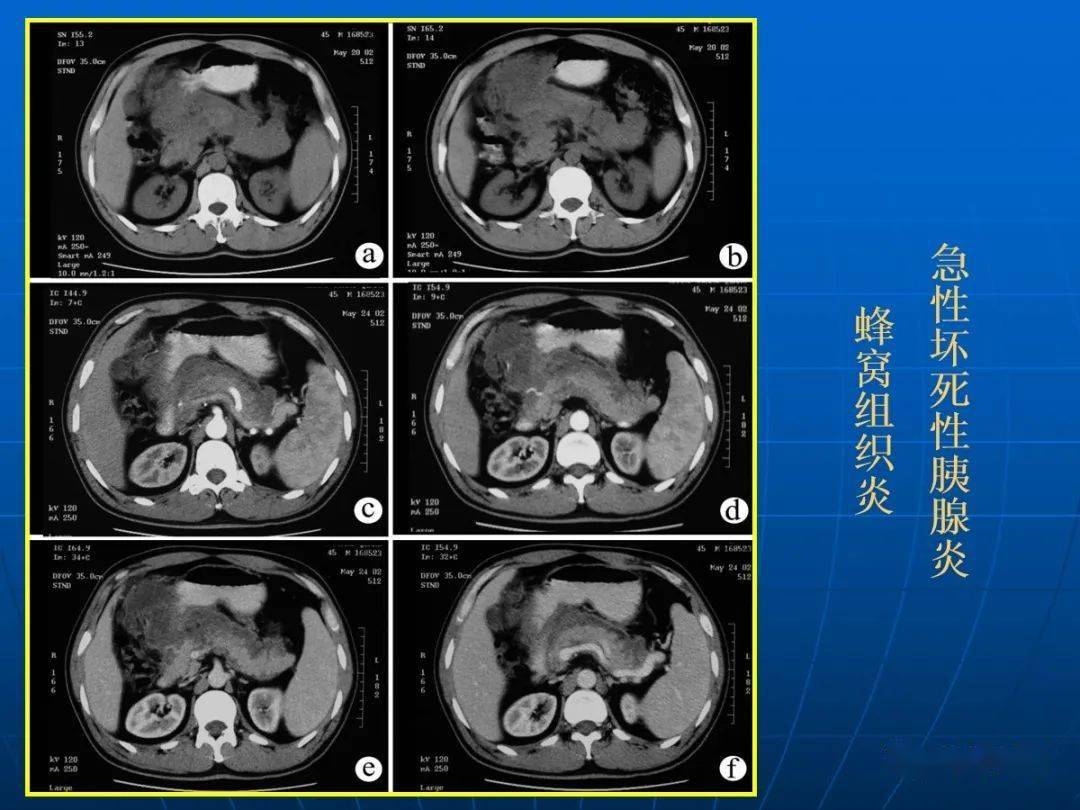

出血坏死型胰腺炎 病史: 饱餐油腻/饮酒后,上腹疼痛 ct特点: 胰腺增大

急慢性胰腺炎的ct影像学分型